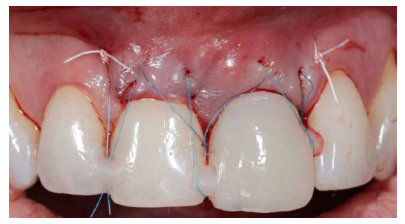

Debido a la presencia de una recesión gingival de 2 mm en el ICSD, el ITC que se obtuvo fue del tamaño suficiente para abarcar la región de este diente y poder tratar dicha recesión de forma simultánea al procedimiento sobre el IOI. Se adaptó a la región receptora con sutura 5.0 de politetrafluiretileno (PTFE) con puntos de fijación en mesial y distal, lo que garantizaba la correcta vascularización del injerto (Figuras 14A, 14B, 14C).

del mismo de forma tunelizada. 14B. Detalle del injerto de tejido conectivo de origen palatino. Se puede observar la longitud del mismo que comprende tanto el alveolo del diente 2.1 así como el diente 1.1 con el fin de mejorar el biotipo gingival y disminuir la recesión gingival presente en el diente 1.1. 14C. Injerto de tejido conectivo tunelizado y fijado mediante sutura PTFE en mesial y distal. Se puede observar el volumen

perioperatorio del tejido blando.

Para terminar el abordaje quirúrgico, se colocó la prótesis provisional con el PE ya confeccionado y se llevaron a cabo tres puntos de tracción coronal con anclajes de los mismos a los puntos de contacto del provisional y dientes adyacentes con sutura monofilamento 6.0 (Figura 16). En la figura 17 se muestra de forma esquematizada el orden del procedimiento en el caso presente.